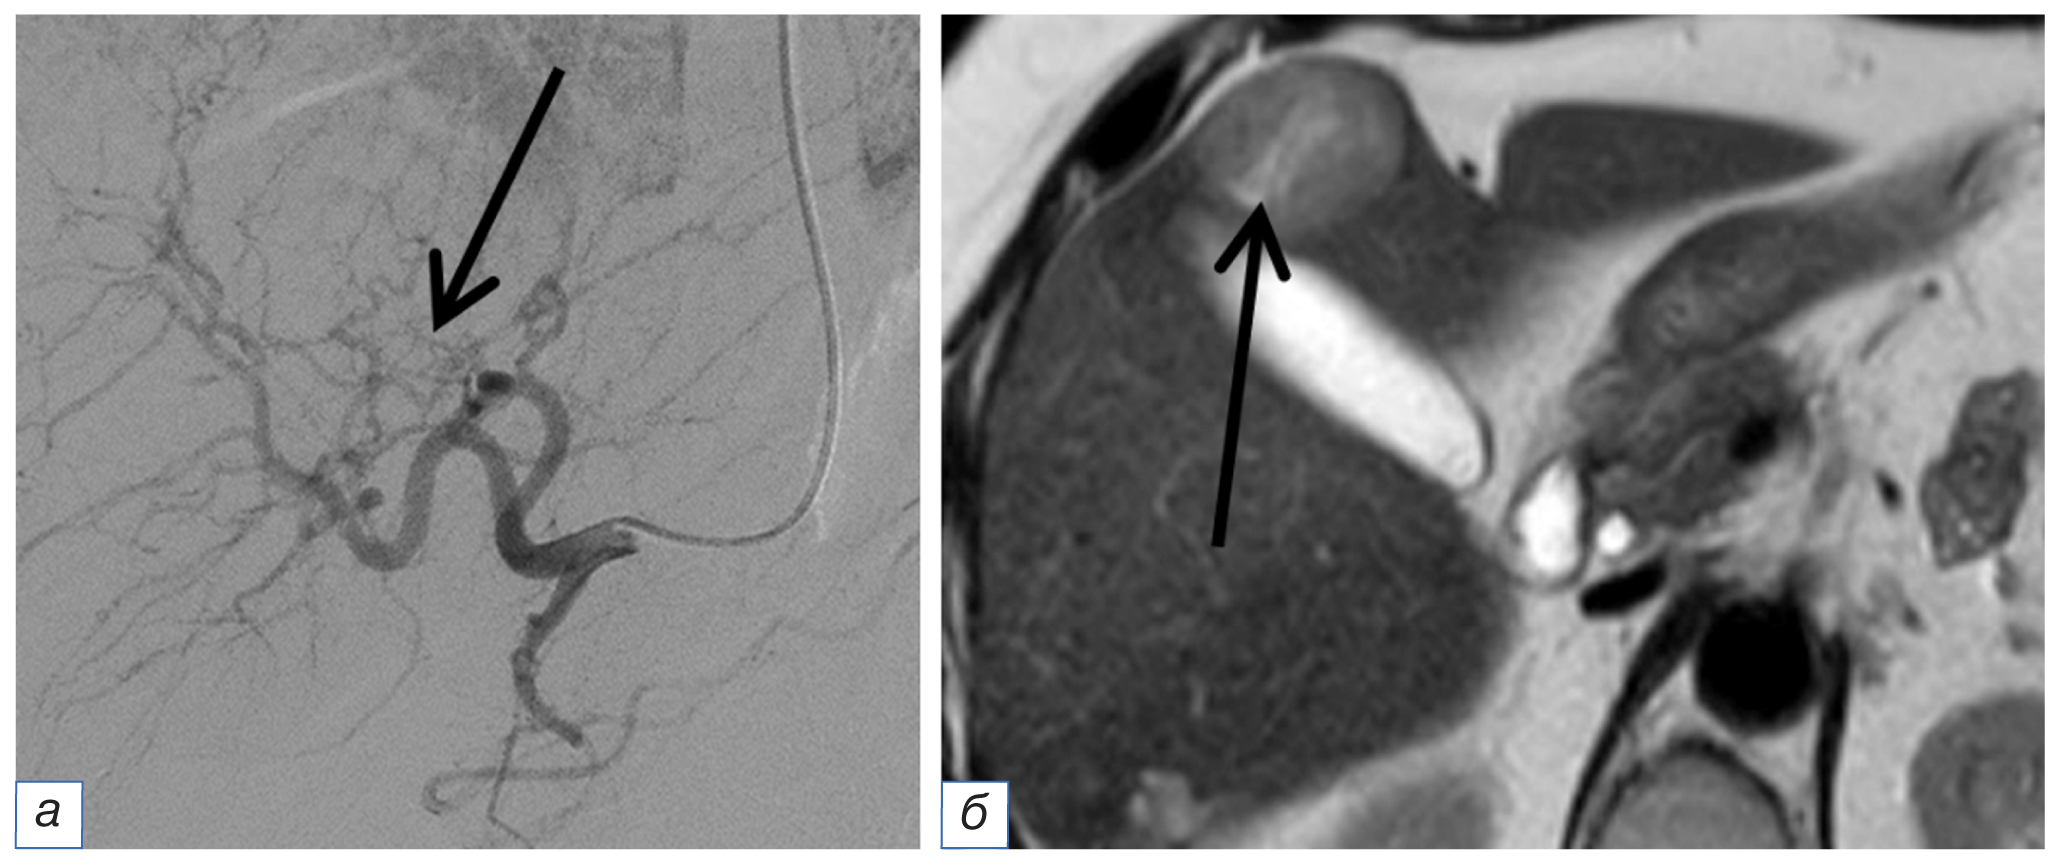

Ангиографическая картина во время операции также была разнообразна. В ряде случаев мы наблюдали достаточно интенсивное контрастирование паренхимы метастаза с разветвленной сетью афферентов (рис. 2), при этом наличие рядом расположенных очагов угадывалось только по перекалиброванным сосудам, отходящим в нетипичном месте (рис. 3). В ряде наблюдений вообще не было ангиографических признаков опухоли: в этом случае рентгенохирург мог ориентироваться только на данные диагностических методов. Заметим, что ангиоархитектоника основной опухоли не совпадала с ангиографической картиной метастазов в печени (рис. 3).

Рис. 2. Ангиография (а): интенсивное контрастирование метастаза диаметром 3 см (стрелка); магнитно-резонансная томография (б): тот же метастаз диаметром 3 см с щелевидным некрозом в структуре (длинная стрелка), инфильтративный метастаз диаметром 0,5 см с локально расширенным желчным протоком в центре (объемная стрелка), опухоль хвоста поджелудочной железы (треугольная стрелка); ангиография опухоли поджелудочной железы (в): разветвленная сеть афферентов (треугольные стрелки). / Fig. 2. Angiography (а): intense contrast of a metastasis with a diameter of 3 cm (white arrow); magnetic resonance imaging (б): the same metastasis with a diameter of 3 cm with slit necrosis in the structure (long arrow), an infiltrative metastasis with a diameter of 0.5 cm with a locally expanded bile duct in the center (3D arrow), the pancreatic tail tumor (triangular arrow); angiography of the pancreatic tumor (в): branched network of afferents (triangular arrows).